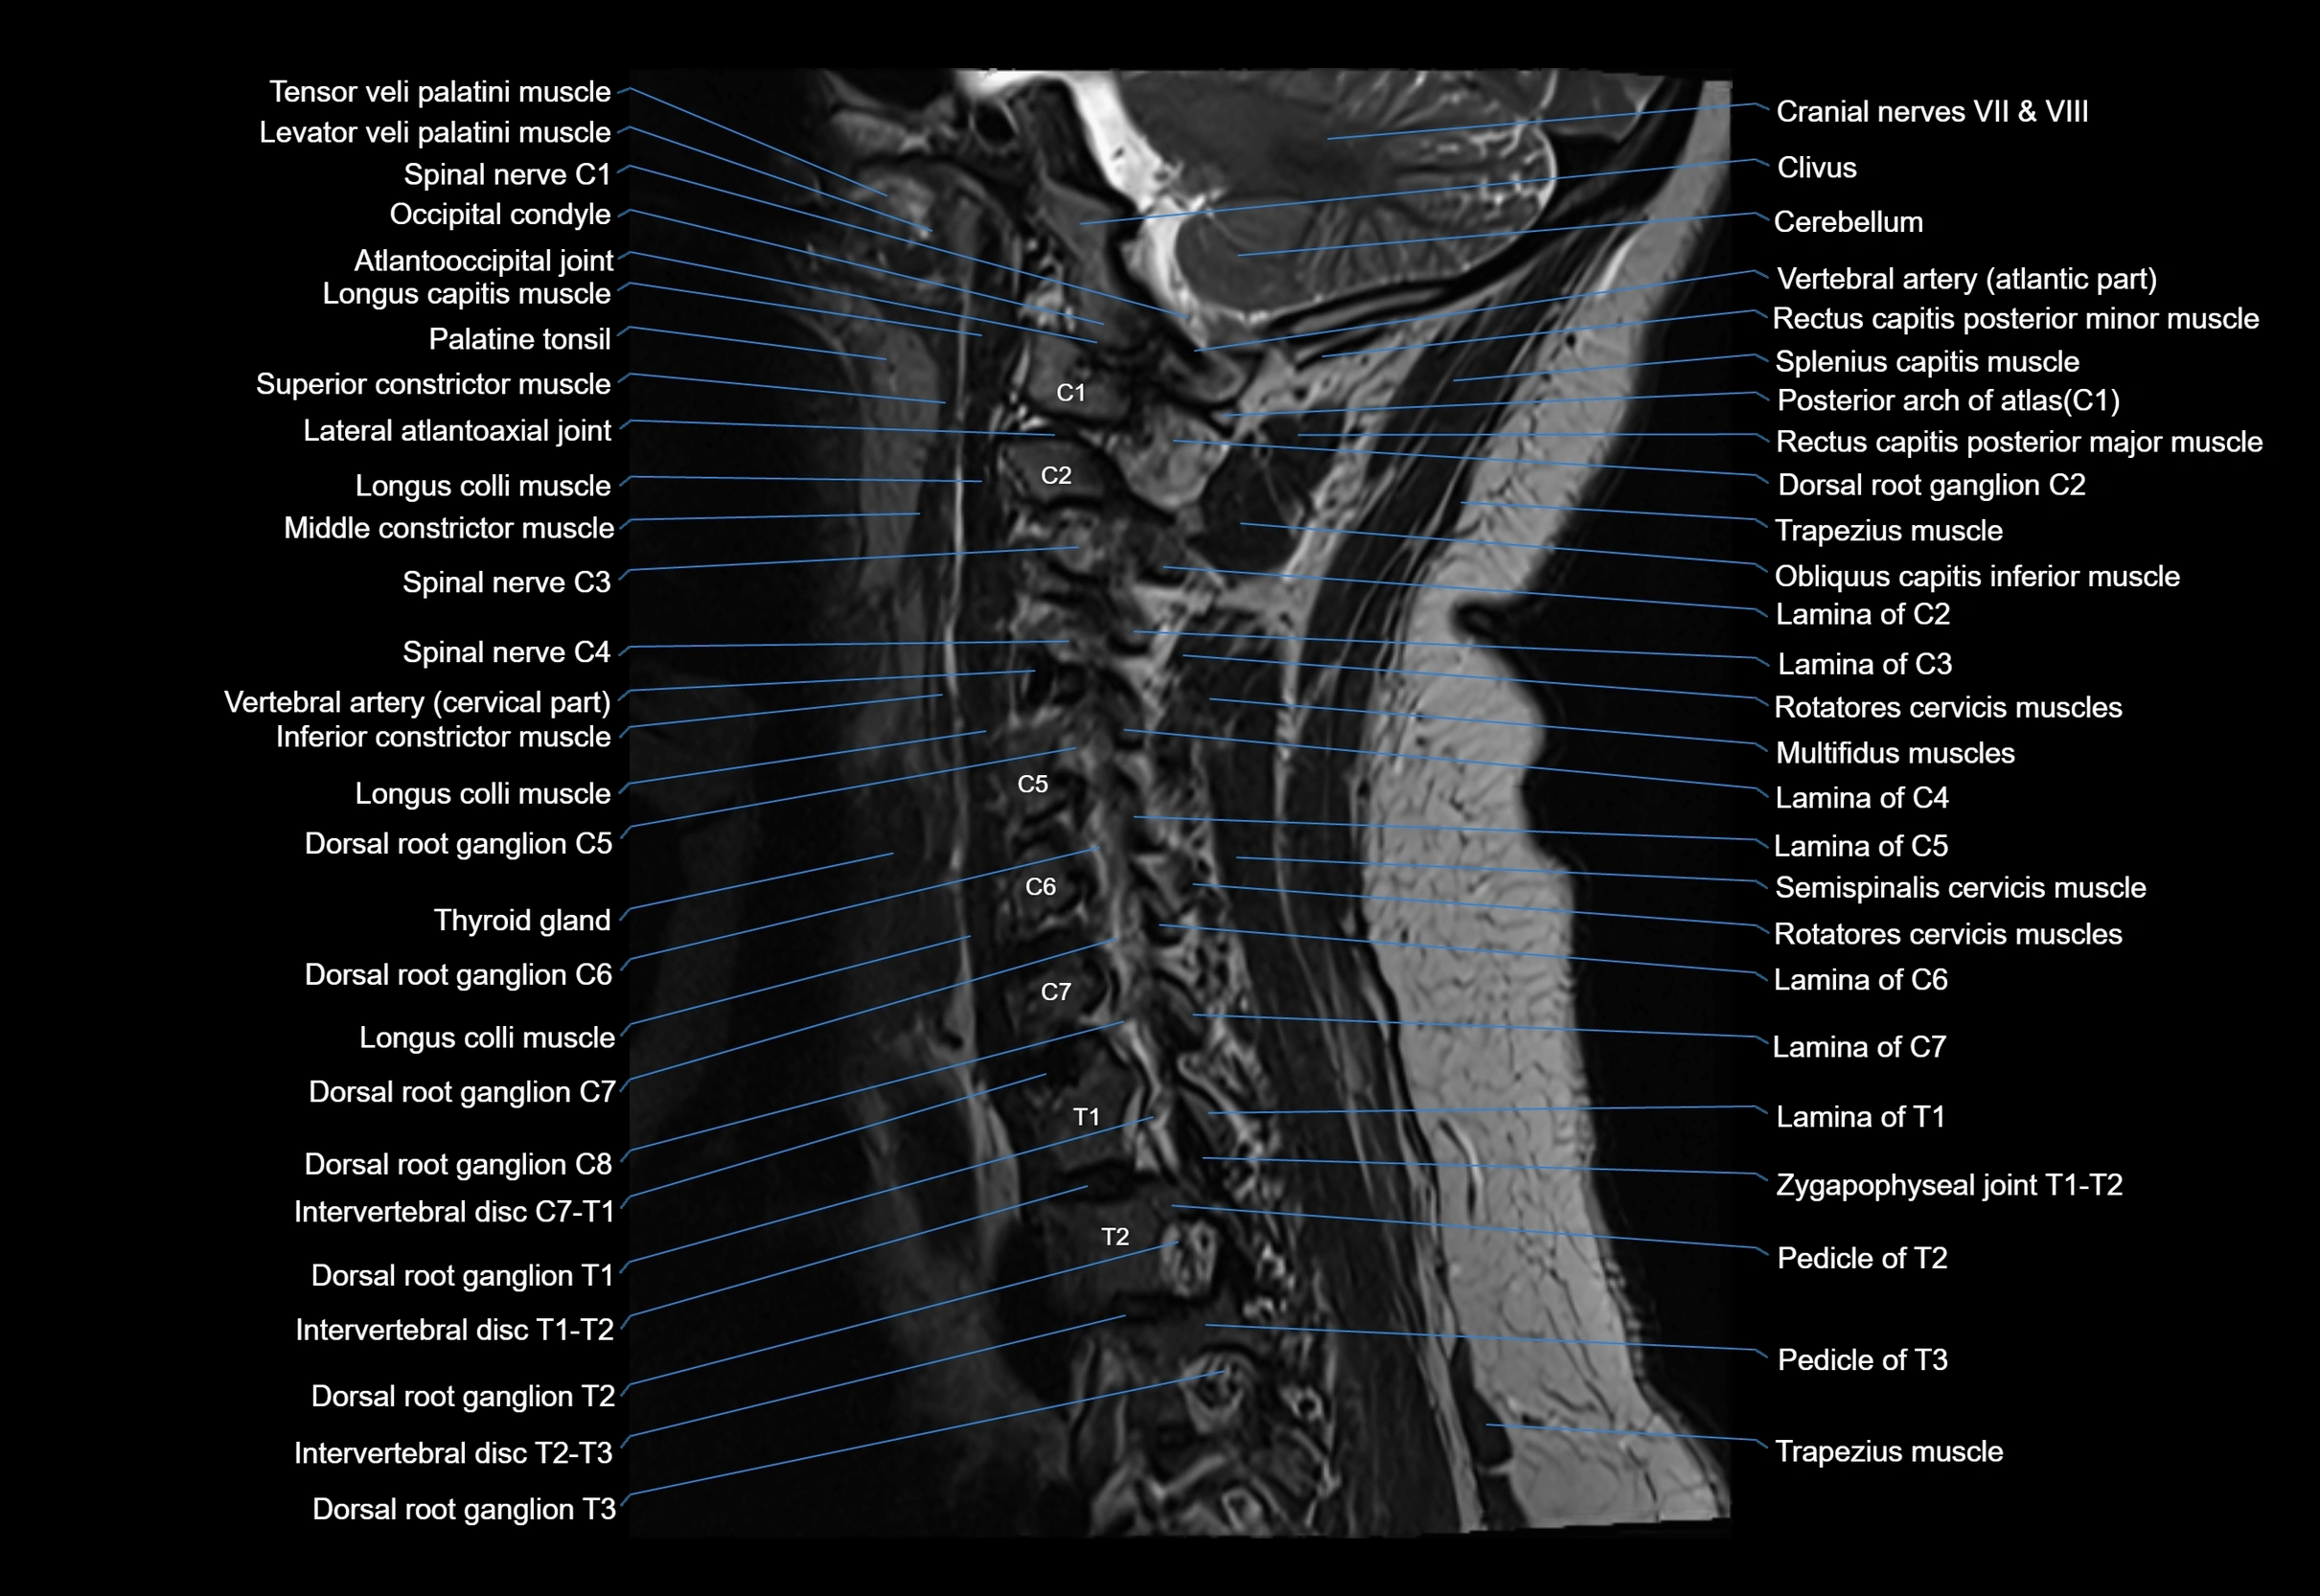

MRI image

image